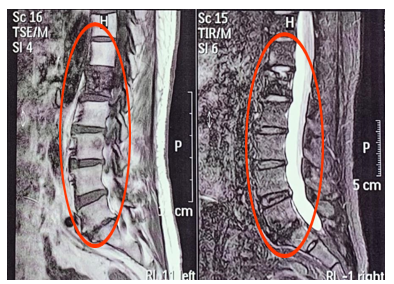

2019月5月核磁(如图4)显示T11, T12, L1,L3, L5 考虑骨转移。PFS2为10个月。

图4 MRI考虑多发骨转移